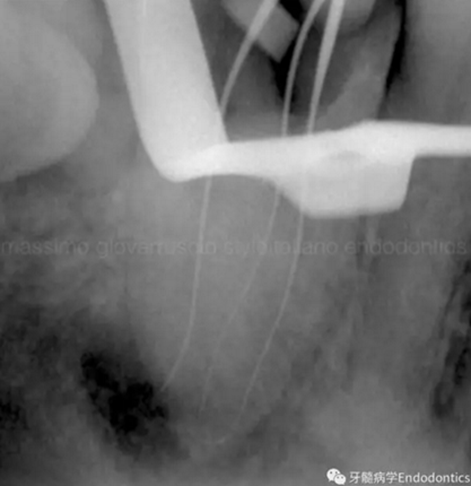

當(dāng)建立直線通路、找到所有的根管口后,重心應(yīng)轉(zhuǎn)移到根管預(yù)備上。若牙髓存在活力且持續(xù)滲血,應(yīng)使髓室內(nèi)充滿粘性螯合劑。在牙髓已壞死的情況下,應(yīng)使用加熱的5.25%次氯酸鈉溶液沖洗并徹底充滿髓室。探查前,根據(jù)術(shù)前X線片測(cè)量并預(yù)彎小的不銹鋼銼,以順應(yīng)預(yù)估的根管長(zhǎng)度及彎曲度。使用0.02錐度的10號(hào)不銹鋼手用K銼探查根管冠方2/3。

圖2.疏通根管冠方2/3后,使用次氯酸鈉溶液沖洗根管,且可以使用手用器械、GG鉆(刷洗動(dòng)作)、旋轉(zhuǎn)鎳鈦成形銼預(yù)敞根管。當(dāng)冠方2/3進(jìn)行了合適的預(yù)備且充滿沖洗液后,接著進(jìn)行根尖1/3的探查以收集信息。使用小的手用銼(8號(hào)或10號(hào)K銼)疏通根管的剩余部分,確認(rèn)建立了流暢的、無阻礙的、平滑的到達(dá)根尖止點(diǎn)的引導(dǎo)通道。